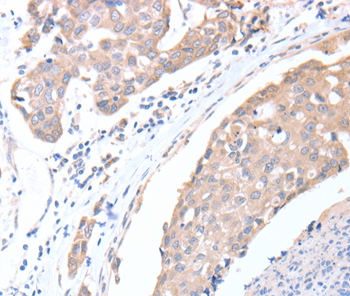

Immunohistochemical analysis of paraffin-embedded Human breast cancer tissue using #36030 at dilution 1/15.